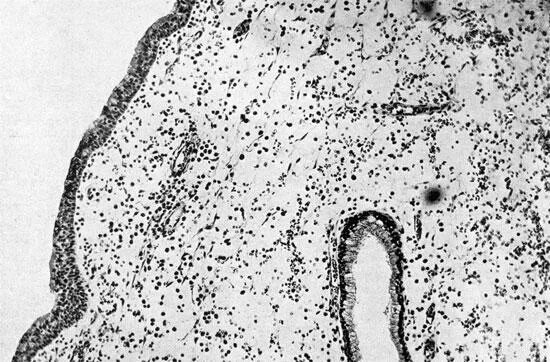

Гистология нос